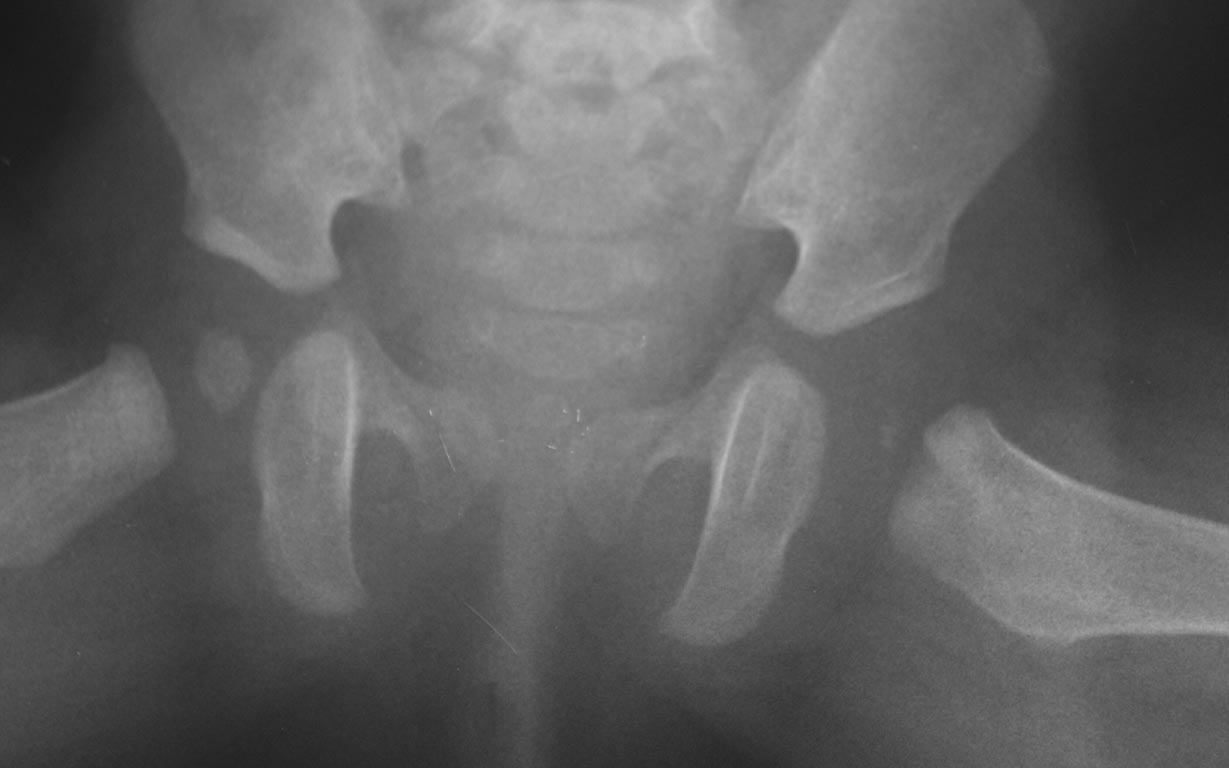

Добрый вечер уважаемые коллеги. Помогите советом, в какую клинику и к

кому обратится с данной проблемой( у ребенка в возрасте 1мес.

диагностирован гематогенный остеомиелит головки бедра). Лечили

консервативно( выписку и фото в динамике прилагаю). На сегодняшний день

ребенку 11 мес. Детские ортопеды по месту сомневаются в тактике( в плане

операции или выжидательная тактика). Хотелось проконсультироваться с

теми кто занимается этой проблемой. Заранее спасибо.